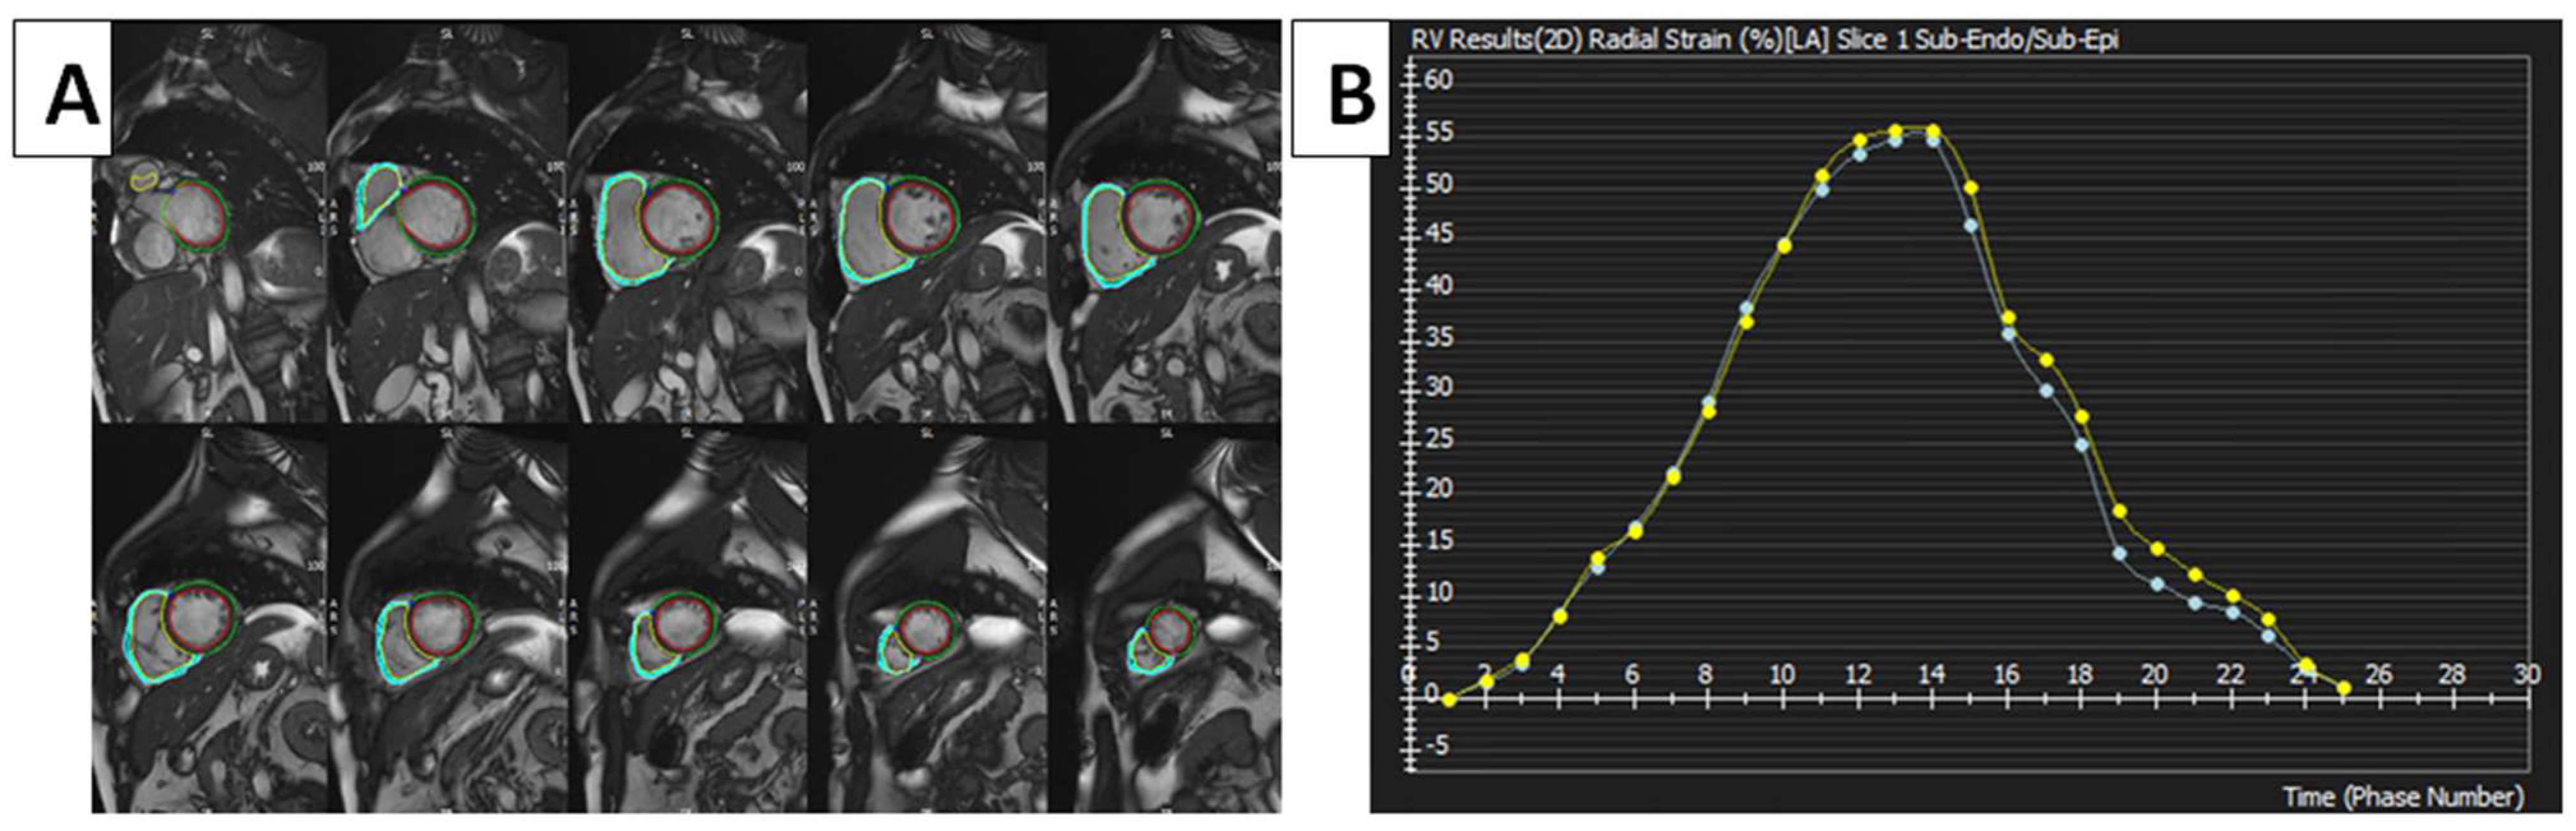

2. RV Mechanical Pattern

3. cMRI Techniques Used to Assess RV Myocardial Strain